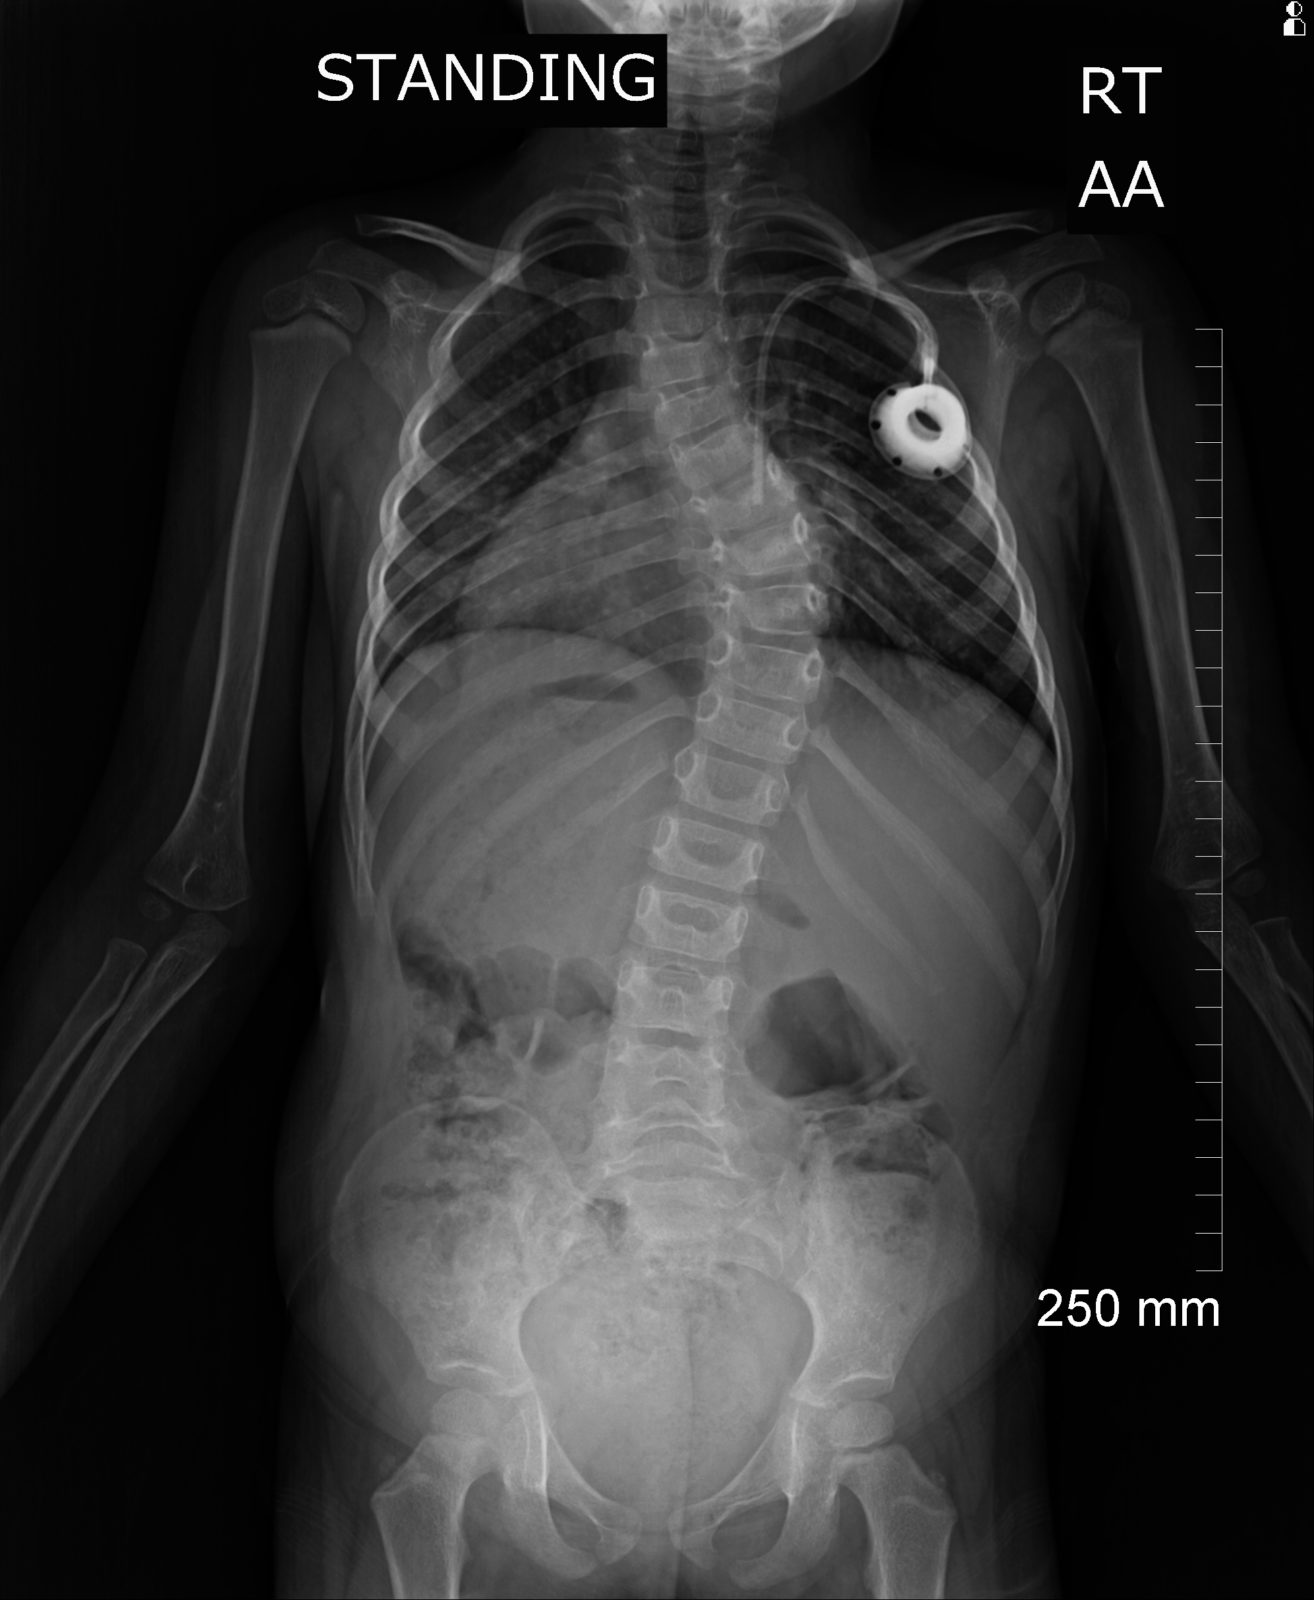

Ok… so the bad news. Scoliosis. Big time. You can see it in the xray. Scoliosis in measured in degrees. 0 is perfect. Up to 25 degrees they monitor and track it. 25-35 and it’s time to wear a brace. North of that and surgery is usually recommended. Havyn’s curve is measuring 46 degrees. The worst portion of the bend is in the same region as the spinal lesion we learned about a couple weeks ago.

We’re reeling a bit from that news. We knew she had it. We had no idea the severity. There is way more we don’t know than what we do know at this point. It’s our understanding that surgery is not an option during chemo. But the orthopedist said she wanted to speak with a bunch of other doctors to help advise us. She was fitted for a brace and we should see that in a few weeks.